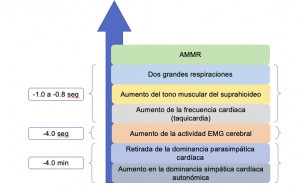

Secuencia de acontecimientos antes de que se produzca un episodio de bruxismo durante la noche

Estudios recientes sugieren que el bruxismo del sueño es secundario a despertares durante el sueño (definidos por un aumento de la actividad cardiaca y respiratoria autónomo, que tiende a repetirse 8-14 veces por hora de sueño). La actividad muscular rítmica que se produce en el sueño picos de bruxismo en los minutos antes de sueño REM. Esto sugiere que existe algún mecanismo relacionado con las transiciones de etapa del sueño que influyen en las neuronas motoras de bruxismo.